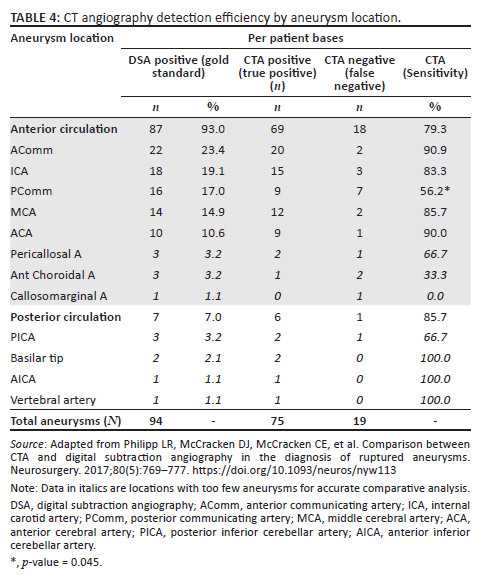

The frequency distribution of aneurysms by vessel of origin and their respective detectability on CTA is demonstrated in Table 4. The pericallosal artery, callosomarginal artery, anterior choroidal artery, posterior inferior cerebellar artery (PICA), basilar tip, anterior inferior cerebellar artery (AICA) and vertebral artery had the minority of aneurysms, each location with three or less aneurysms, thus these locations were not included in the comparative statistical analysis.

There was no statistically significant difference in CTA sensitivity for aneurysms arising from the anterior versus the posterior circulation (p = 0.71), however, the posterior circulation aneurysms were remarkably fewer in number. The CTA sensitivity (56.2%) for aneurysms arising from PComm was significantly poor compared with the rest of the major anterior circulation locations (AComm, ACA, MCA and ICA) (83% - 91%) and the overall CTA sensitivity (80%) (p = 0.045).

In this single, tertiary institution study we retrospectively evaluated the diagnostic accuracy of CTA for detecting ruptured intracranial aneurysms using DSA as a reference standard. The CTA diagnostic performance was limited, with sensitivity, specificity, PPV, NPV and accuracy of 80%, 43%, 86%, 32% and 73%, respectively. The CTA diagnostic efficiency was even lower for multiple aneurysms because of failure to detect all additional, non-causative aneurysms. Very small aneurysms with diameters < 3 mm were difficult to detect on CTA (sensitivity of 30%), while there was a drastic improvement in sensitivity for aneurysms ≥ 3 mm with sensitivities from 81.5%. There was no significant difference between the CTA sensitivity for anterior versus posterior circulation aneurysms, even though the vast majority of aneurysms were located in the anterior circulation. Aneurysms arising from PComm were difficult to detect on CTA (sensitivity of 56%), whereas CTA sensitivity was not adversely affected in the rest of the major anterior circulation locations, namely anterior communicating artery (AComm), anterior cerebral artery (ACA), middle cerebral artery (MCA) and internal carotid artery (ICA).

Diminished CTA sensitivity for very small aneurysms (≤ 3 mm) is well documented in the literature,11,15,17 which is congruent to this study. In contrast Lu et al. demonstrated good CTA sensitivity even for aneurysms < 3 mm in size using dual energy CTA.12 Some authors reported no difference in CTA sensitivity for anterior versus posterior circulation aneurysms.11,12 This finding is supported by this study, even though the aneurysm frequency proportions were markedly skewed towards the anterior circulation. Several studies reported lower CTA sensitivity for locations close to the bony base of skull such as the ICA14,15 and PComm.19 The latter was congruent with the findings of this study, which demonstrated significantly lower PComm sensitivity (56%) compared with other major anterior circulation locations. The ICA location however did not show significantly compromised CTA sensitivity in this study (Figure 2).